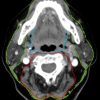

* Phân chia khoang vùng cổ: Vùng cổ được chia làm 2 phần trên và dưới dựa vào xương móng gồm vùng cổ trên móng và vùng cổ dưới móng. 3 lá mạc cổ sâu chia cổ thành nhiều khoang:

– Mạc cổ sâu, lá nông (SL-DCF: superficial layer, deep cervical fascia)

+ Cổ trên xương móng: vòng quanh khoang nhai và khoang mang tai; một phần bao cảnh

+ Cổ dưới xương móng: bao quanh cổ bởi các cơ treo, cơ ức đòn chũm và cơ thang.

– Mạc cổ sâu, lá giữa (ML-DCF: middle layer, deep cervical fascia)

+ Cổ trên xương móng (SHN): ML-DCF vạch rõ bờ sâu khoang niêm mạc hầu; góp vào bao cảnh.

+ Cổ dưới xương móng (IHN): bao quanh khoang tạng; một phần bao cảnh

– Mạc cổ sâu, lá sâu (DL-DCF: deep layer, deep cervical fascia)

+ SHN và IHN: bao quanh khoang cạnh cột sống

+ SHN và IHN: góp vào bao cảnh

+ SHN và IHN: mạc cánh là lá mỏng của DL-DCF tạo nên thành ngoài của khoang sau hầu và khoang nguy hiểm; cũng như thành sau khoang sau hầu tách từ khoang nguy hiểm.

* Cổ trên xương móng (SHN: suprahyoid neck): Các khoang từ nền sọ tới xương móng (ngoại trừ ổ mắt, các xoang và ổ miệng).

– Khoang bên hầu (PPS: parapharyngeal space).

– Khoang niêm mạc hầu/bề mặt niêm mạc hầu (PMS: pharyngeal mucosal space).

– Khoang nhai (MS: masticator space).

– Khoang cảnh (CS: carotid space).

– Khoang má (BS: buccal space).

– Khoang sau hầu (RPS: retropharyngeal space).

– Khoang quanh cột sống (PVS: perivertebral space).